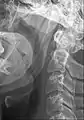

Ligament stylo-hyoïdien ossifié ou processus styloïde allongé.

Le ligament stylo-hyoïdien contient fréquemment un peu de cartilage en son centre. Celui-ci peut s'ossifier, allonger l'apophyse styloïde et entraîner un syndrome d'Eagle.